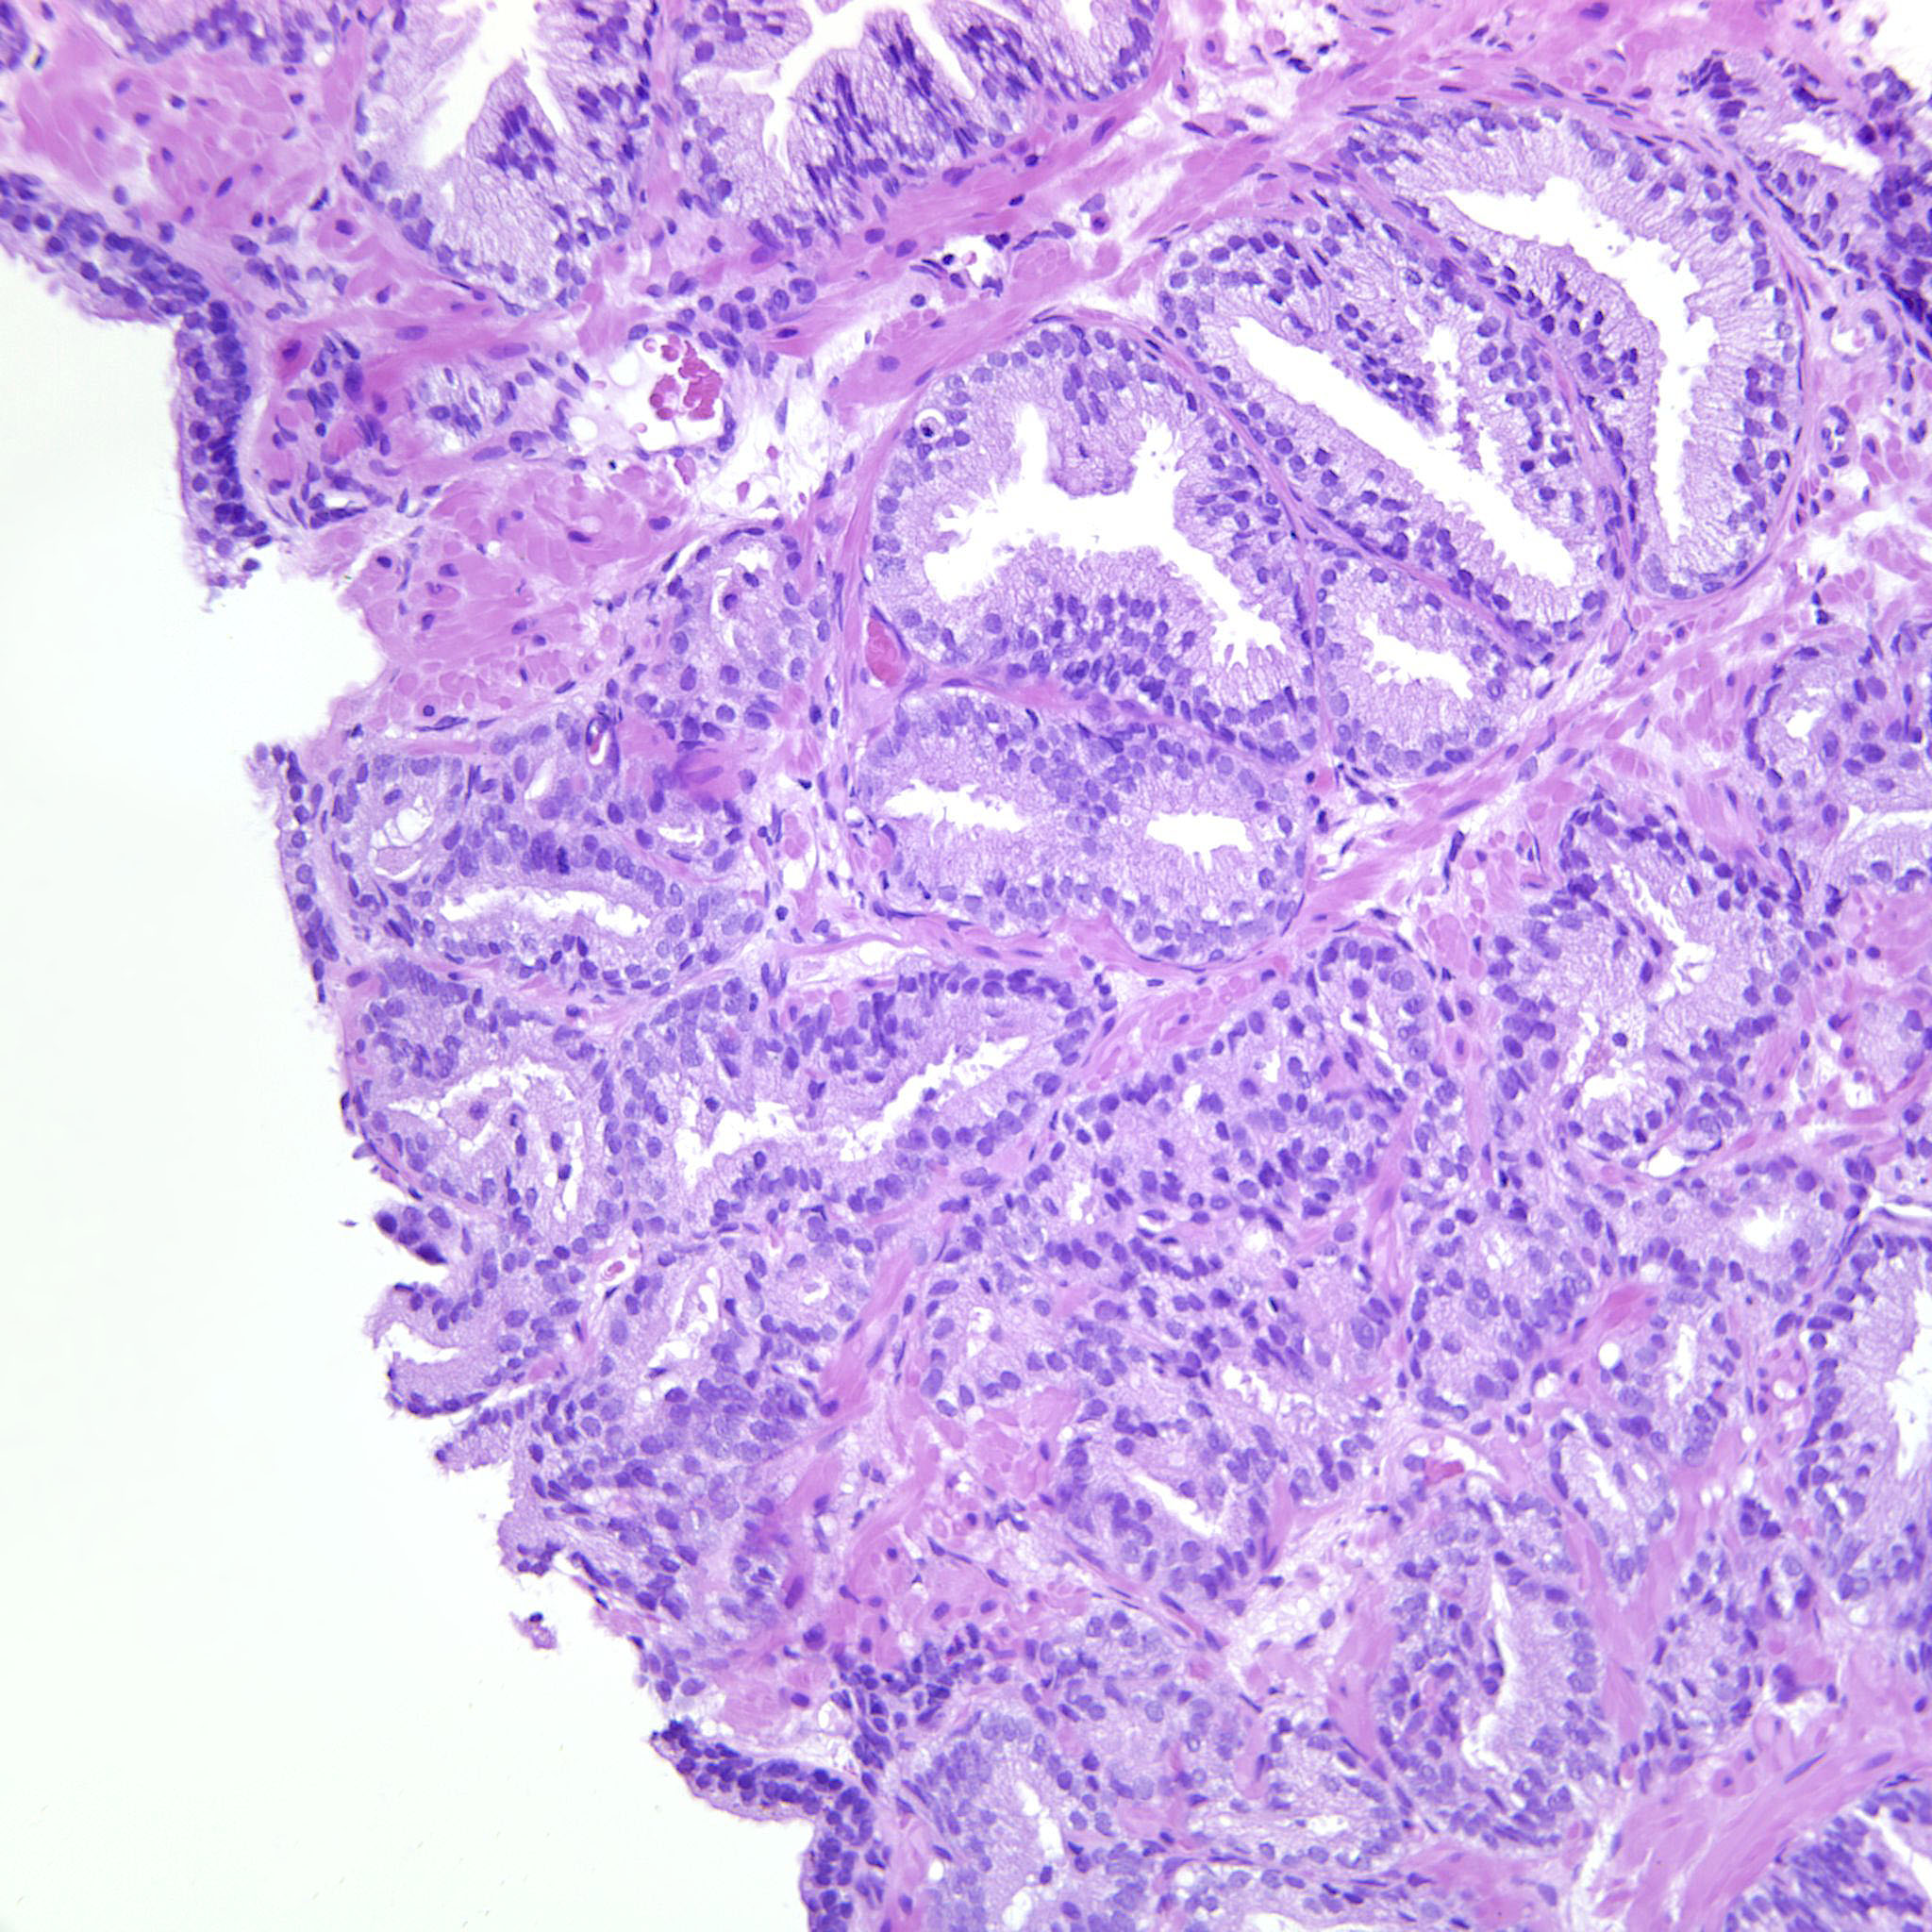

Prostate cancer grading

Case ID: 738